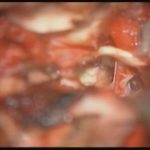

術中写真

摘出 中